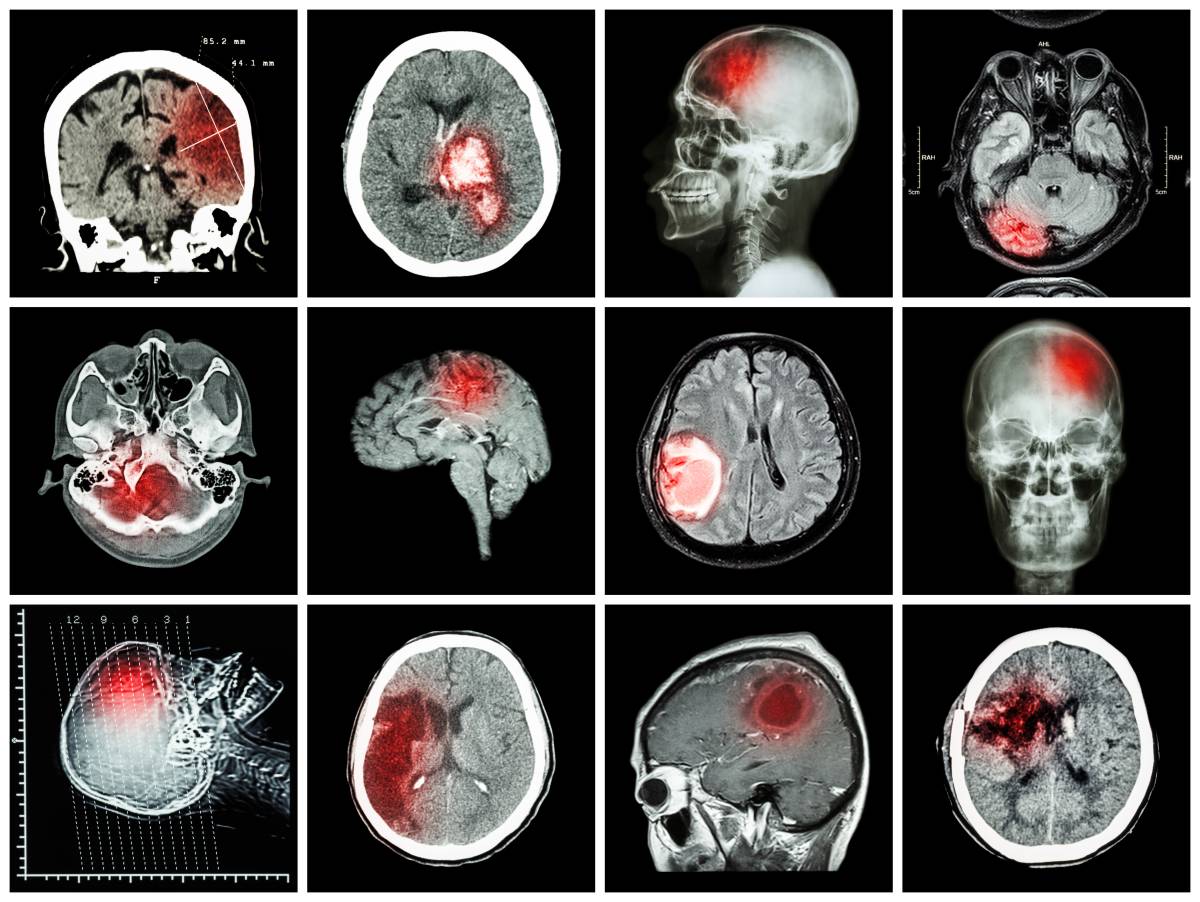

脑出血,指的是一种非外伤性的脑实质内出血,发病因素多样,但大多都是由于高血压小动脉硬化引起的血管破裂所导致。临床统计表明,高血压患者有三分之一的概率会出现脑出血;而在脑出血患者中,有超过90%的患者伴有高血压。脑出血有着极高的致残、致死率,属于现阶段我国脑血管病中死亡率最高的疾病。

据调查,脑出血患者年龄主要集中在50~70岁,大多数患者是在情绪激动、运动量过大时发病,主要表现为:头晕头痛,这是最为常见的症状,且几乎所有脑出血患者都会出现,一般会发生在出血位置,随着出血量的增加,会逐渐蔓延至整个头部;运动障碍,指的是单侧肢体无力或瘫痪,生活无法自理,不能独立进行活动;语言障碍,指的是失语或言语不清,说话无法连成句,且对他人提出的问题无法进行完整回答;意识障碍,主要是因为脑出血患者会同时伴有昏迷状况,这与出血位置及出血量均相关,如果出血点的位置在脑深处,且短时间内出血较多,就会造成意识障碍;呕吐,主要是因为脑出血会导致颅内压增高,出现眩晕现象的同时脑膜也在受着血液的刺激,有研究表明,该症状的出现概率约占到脑出血患者的二分之一;眼部症状,主要是因为脑出血所引起的颅内压增高,会导致脑疝现象,从而引发一系列的眼部症状,如眼球活动障碍、瞳孔等大、偏盲等,如果是急性脑出血,还会出现凝视麻痹现象,导致双眼凝视大脑出血侧。